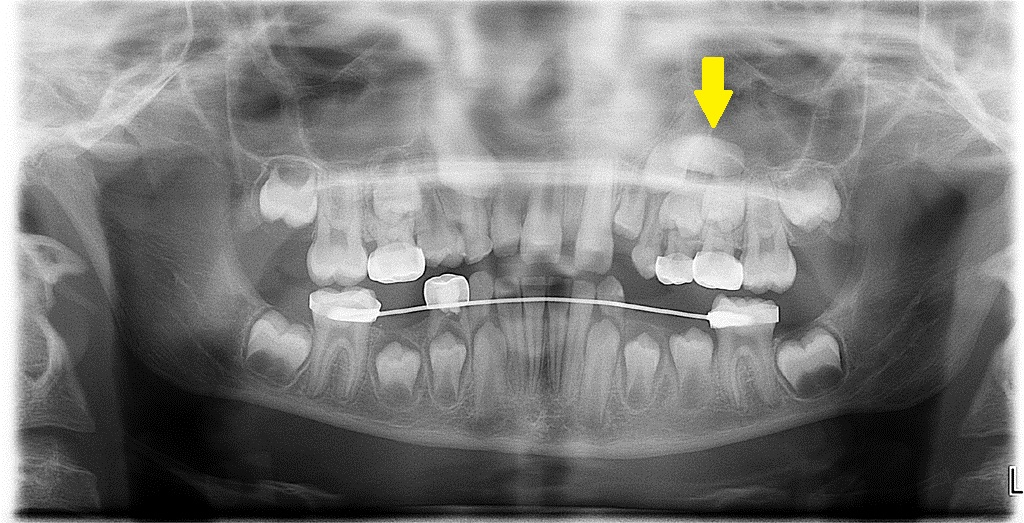

1. What condition can be seen in the following X ray? ( solid arrow)

the calcification within Stensen's duct of parotid